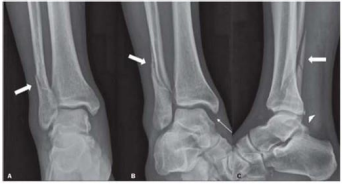

Um paciente de 45 anos de idade sofreu entorse do tornozelo direito durante prática de skate. No hospital, foram realizadas as radiografias representadas na figura.